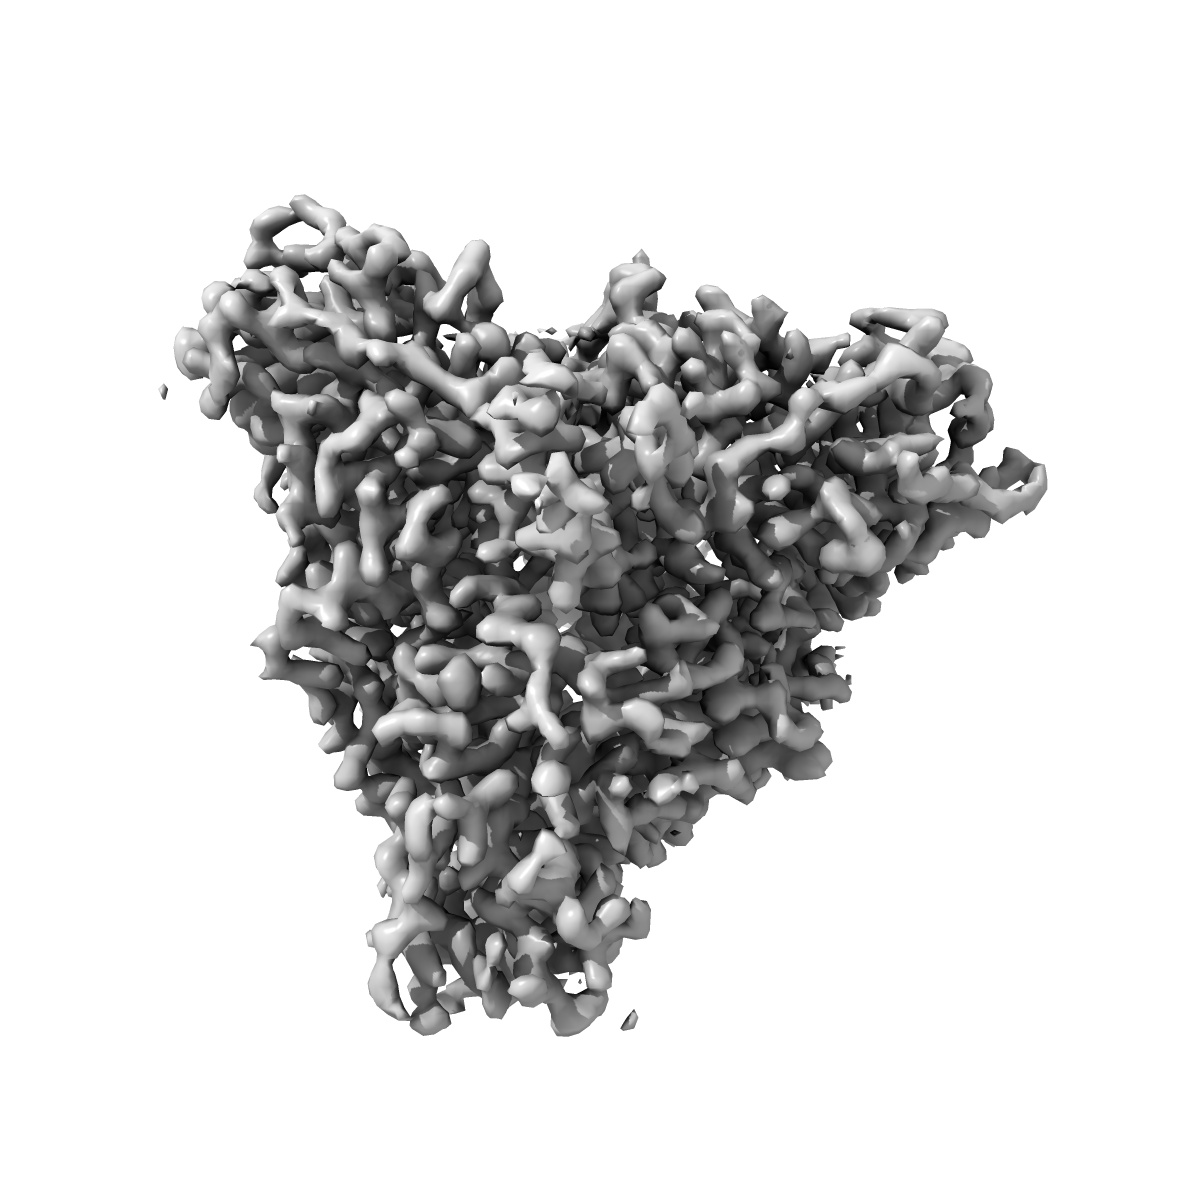

Nipah virus (NiV) fusion protein in complex with neutralizing Fab92

Single-particle3.5 Å

Sample: Nipah virus fusion (F) glycoprotein in complex with Fab92

A monoclonal antibody targeting the Nipah virus fusion glycoprotein apex imparts protection from disease.